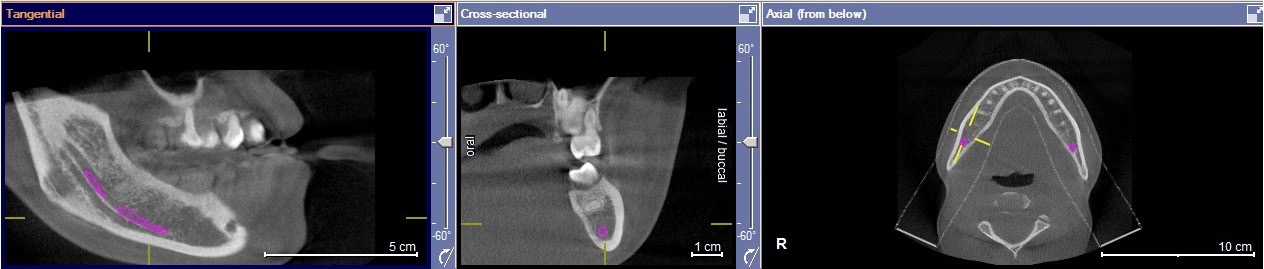

All molar teeth were evaluated in 3 planes (sagittal, axial and coronal) to determine the shortest linear distance between the root apex and the superior cortical border of MC (Figure 1). Distances <1.00 mm were classified as very close to MC (Figure 2).28 Distances ≥1.00 mm were considered distant from MC (Figure 3).28 When the root apex was in intimate contact with or invading MC, the distance was recorded as 0 mm (Figure 4).